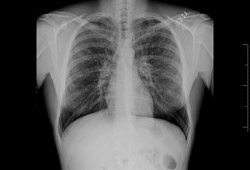

Radiografia torácica com vias aéreas dilatadas e espessadas

Dos arquivos do Dr. Sangeeta M. Bhorade; uso autorizado